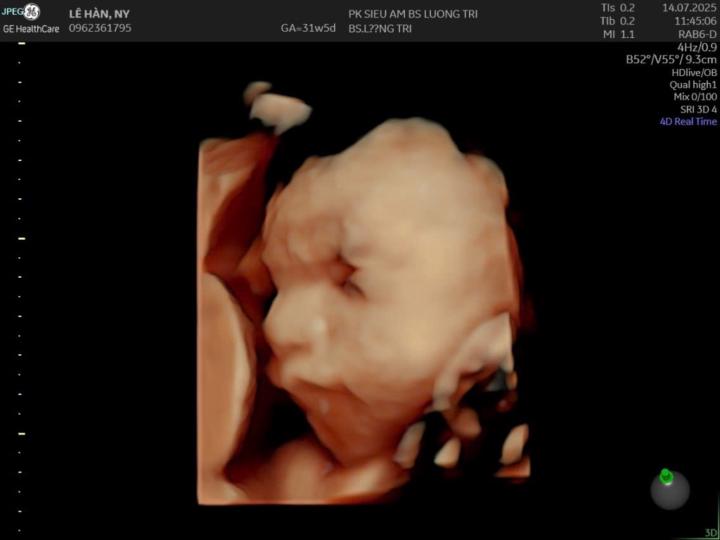

Ny Han

@ny-han-2473

Mẹ Dừa bổ sung kiến thức

Active 6d ago

Joined Mar 9, 2026